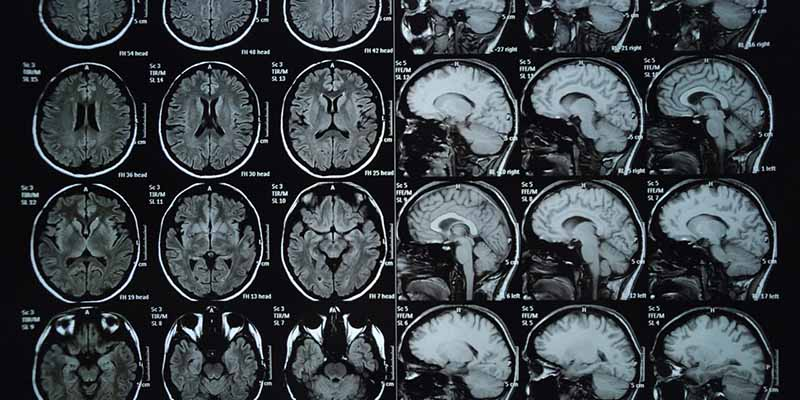

3. Chụp cộng hưởng từ (Magnetic Resonance Imaging – MRI)

Một lựa chọn khác để chụp các hình ảnh cắt ngang là MRI. Tương tự như chụp CT, MRI được sử dụng hiệu quả để chụp ảnh các mô mềm như nội tạng và gân. Không giống như chụp CT, chụp MRI không sử dụng bức xạ ion hóa, thay vào đó máy sử dụng từ trường mạnh và sóng vô tuyến. Do không sử dụng phóng xạ nên MRI thường được cho là an toàn hơn, nhưng chúng cũng mất nhiều thời gian hơn để thực hiện. Trong khi chụp CT có thể mất ít nhất năm phút thì MRI có thể mất tới nửa giờ hoặc lâu hơn tùy thuộc vào quy trình.

Người bệnh sẽ nằm in trên một chiếc bàn trượt và trượt vào máy quét MRI có hình ống. Máy MRI tạo ra từ trường xung quanh người bệnh và sau đó phát sóng vô tuyến đến khu vực của cơ thể cần được kiểm tra. Một máy tính được sử dụng để ghi lại chuyển động của các bộ phận khác nhau như gân, dây chằng, dây thần kinh, … và chuyển dữ liệu thành hình ảnh hai chiều. Người bệnh sẽ không cảm thấy đau khi thực hiện chụp MRI, nhưng máy có thể bị ồn.

MRI có thể được sử dụng để giúp chẩn đoán các bệnh lý dây chằng và sụn đầu gối bị rách, thoát vị đĩa đệm, thoái hóa xương, u xương và các vấn đề khác. Thời gian thực hiện kỹ thuật này có thể mất từ 30 đến 60 phút.